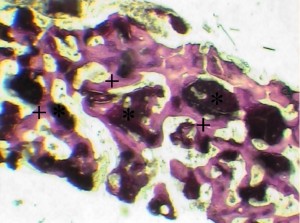

Los macrófagos que migran hacia el tumor se llaman macrófagos o TAMs asociados al tumor, para abreviar. Extensa infiltración de TAM en el tumor a menudo se correlaciona con un peor pronóstico en varios tipos de cáncer. Estos TAM suprimen el sistema inmunitario y estimulan la formación de vasos sanguíneos estimulando así el crecimiento del tumor. Por otro lado, también hay estudios que muestran el efecto contrario, llegando a la conclusión de que TAM tienen un efecto anti-tumoral.

Andrea Casazza y sus colegas, bajo la dirección de Massimiliano Mazzone, estudiaron el mecanismo que es responsable de los fenotipos opuestos de TAM. Su estudio mostró que la proteína neuropilina 1 ( NRP1 ) es crucial para la localización de TAM dentro regiones tumorales hipóxicas , que refuerza las características pro – tumorales de TAM.

En consecuencia, descubrieron que mediante el bloqueo de NRP1, macrófagos ya no fueron capaces de migrar dentro de regiones hipóxicas en el tumor. Es de esta manera que se restaura la actividad anti – tumoral de los macrófagos. Menos supresión de la respuesta inmune y menos formación de vasos sanguíneos en el tumor conduce a una menor crecimiento del tumor .

Además, estos resultados también tienen un importante valor – el posicionamiento de los macrófagos en regiones tumorales hipóxicas sería una indicación de un mal pronóstico, mientras que la localización de los macrófagos en las regiones normóxicas del tumor podría predecir un mejor resultado de la enfermedad de pronóstico.